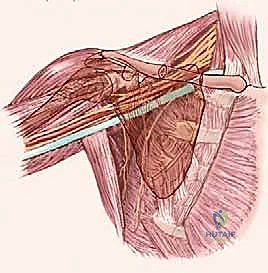

الخطوة الثالثة: الاستكشاف والفصل الميكروسكوبي

هذه هي المرحلة الأكثر حساسية. باستخدام أدوات الجراحة الميكروسكوبية والعدسات المكبرة، يبدأ الدكتور هطيف بتحديد الشريان الإبطي، الوريد الإبطي، وحزم الضفيرة العضدية العصبية. يتم فصل هذه الهياكل الحيوية عن الورم ببطء ودقة شديدة (مليمتر بمليمتر).

الخطوة الرابعة: استئصال الورم (Tumor Excision)

- في الأورام الحميدة: يتم استئصال الورم بالكامل مع الحفاظ على الكبسولة المحيطة به لضمان عدم ترك أي بقايا.

- في الأورام الخبيثة: يتم تطبيق مبدأ "الاستئصال الجذري الواسع" (Wide Local Excision)، حيث يتم استئصال الورم مع حافة من الأنسجة السليمة المحيطة به لضمان إزالة جميع الخلايا السرطانية المجهرية ومنع عودة الورم.